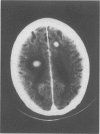

In the majority of cases plasma cell leukaemia is a rapidly fatal disease with a mean survival time of five months. There have been reports of increased survival using various regimens of chemotherapy although most cases eventually relapse. We describe a patient with primary plasma cell leukaemia who responded to a combination of oral melphalan and prednisolone with control of the disease in the bone marrow but relapsed with extramedullary disease in the central nervous system and testes, and died 22 months after diagnosis. Melphalan poorly penetrates the central nervous system and its testicular penetration is unknown.